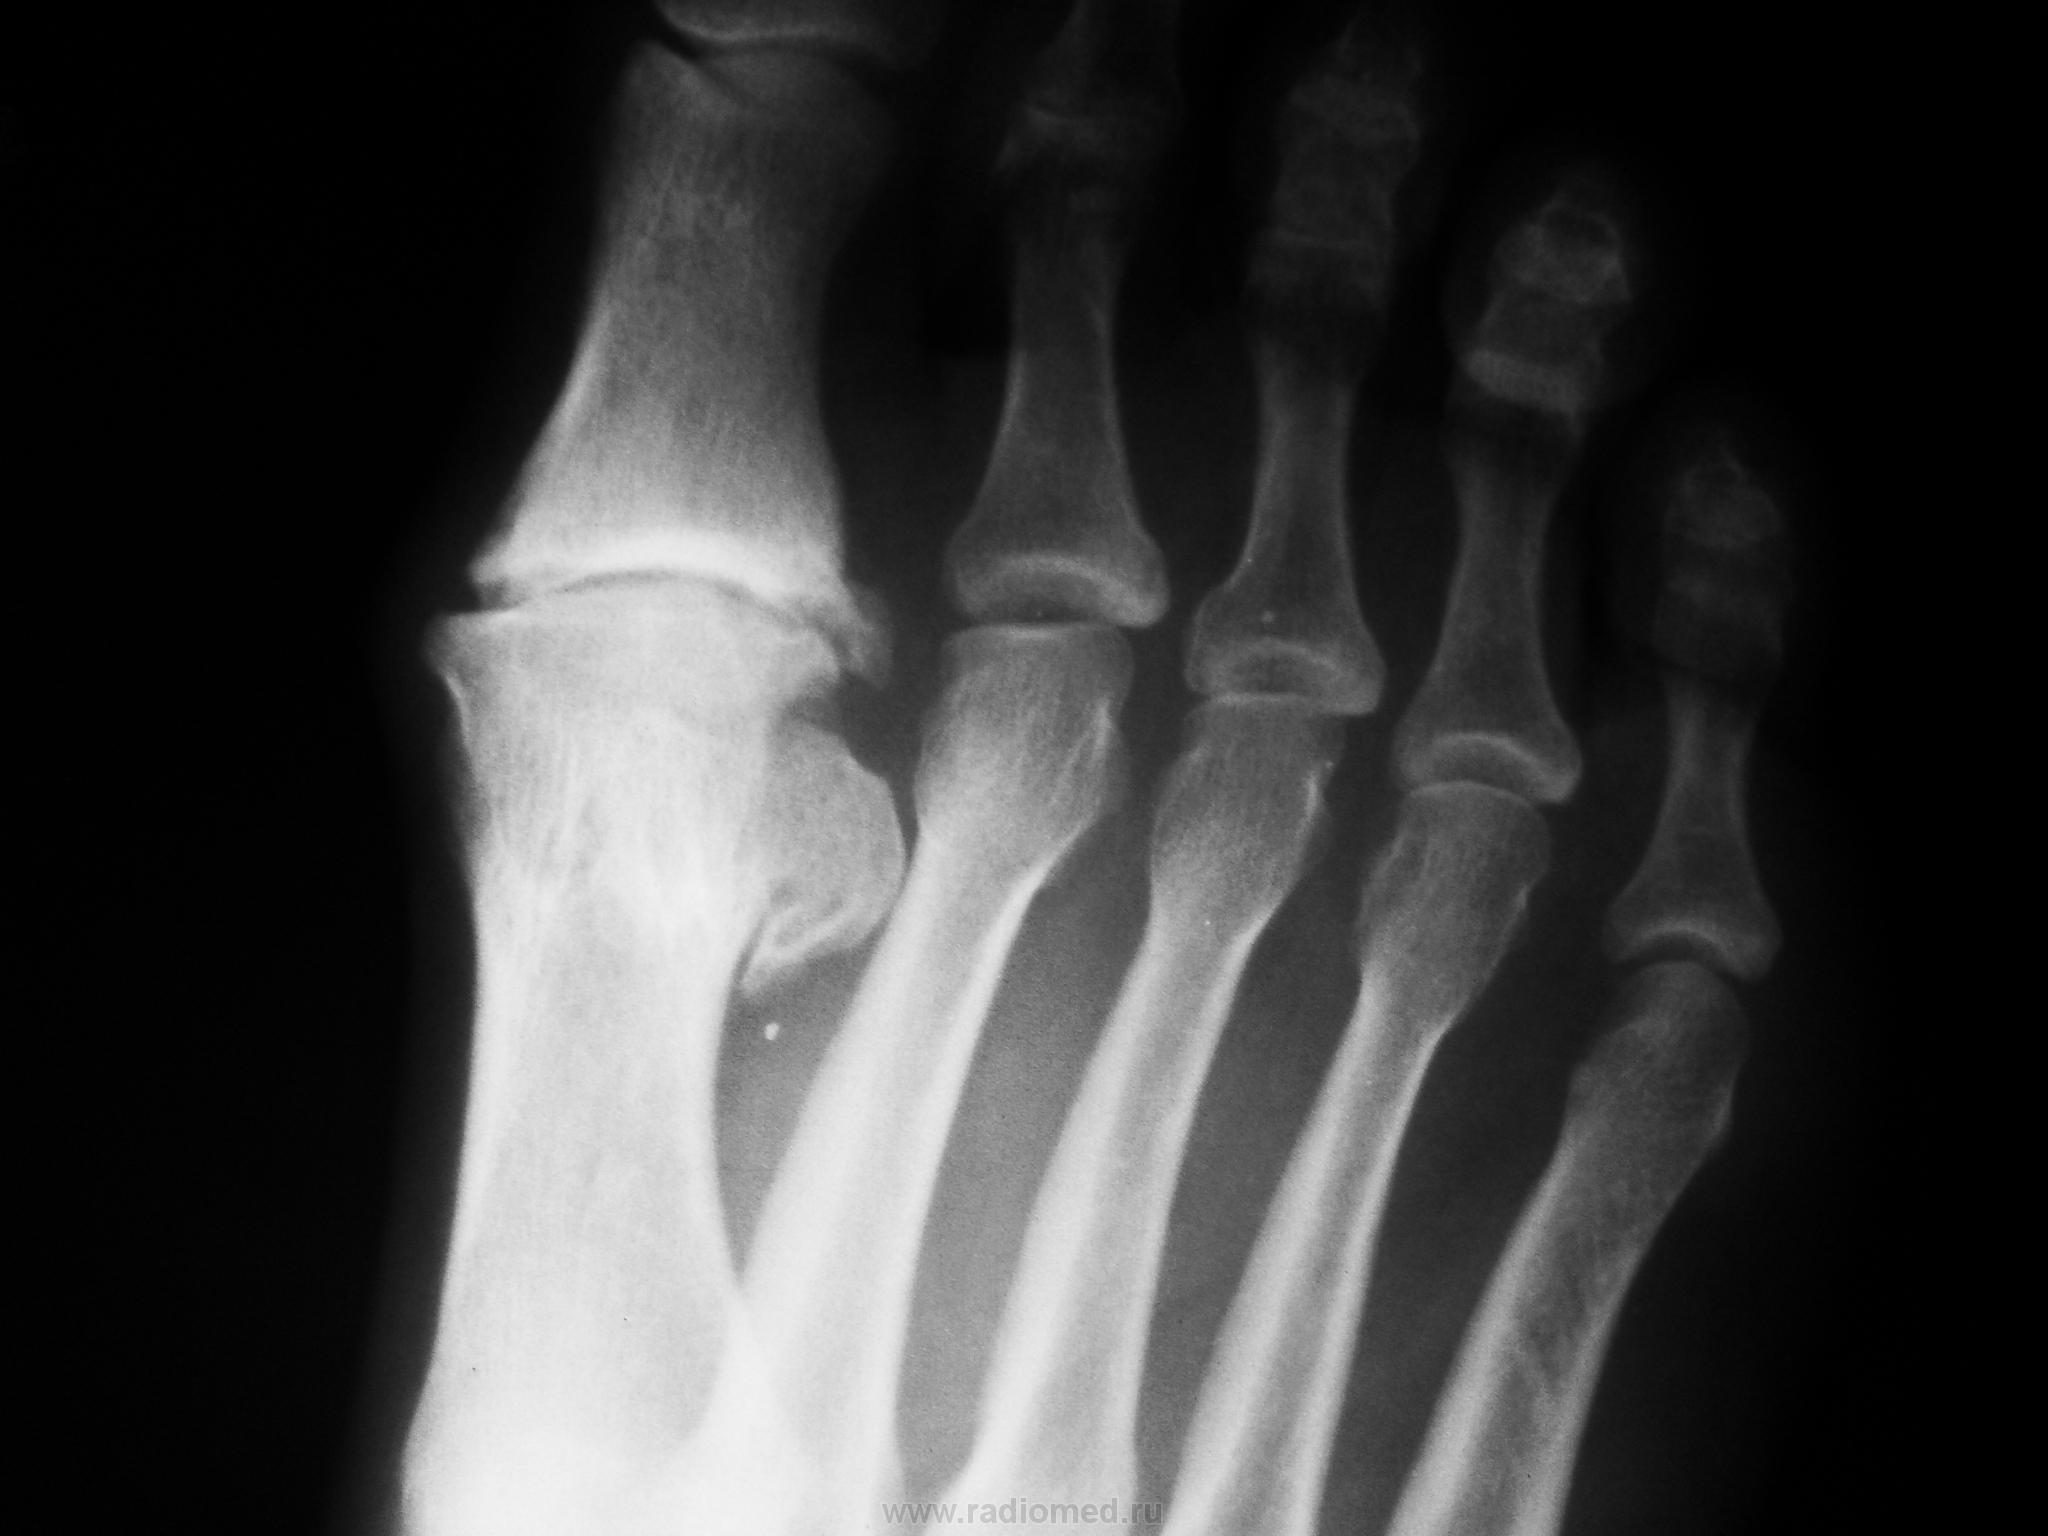

Один из методов лечения поперечного палоскостопия с выраженым дефартрозом 1 пл-ф суст. Операция Вредена-Мейо+ операция Брандеса+формирование поперечной связки стопы+протезирование. Померяйте какой сейчас Hallux valgus, опишите состояние культи и протеза.

Уважаемая Медея(вот красивое имя у Вас), к сожалению с протезированием данного сустава я не сталкивался, скажите Вы выставили первичный снимок до операции ( вальгус там не большой), какие причины сподвигли докторов заменить сустав? боль? нарушение опоры, ходьбы?у Вас это рядовая операция или "будем пробовать" , с таким варусом сложно обувь подобрать, поперечный свод стопы стал еще шире.....